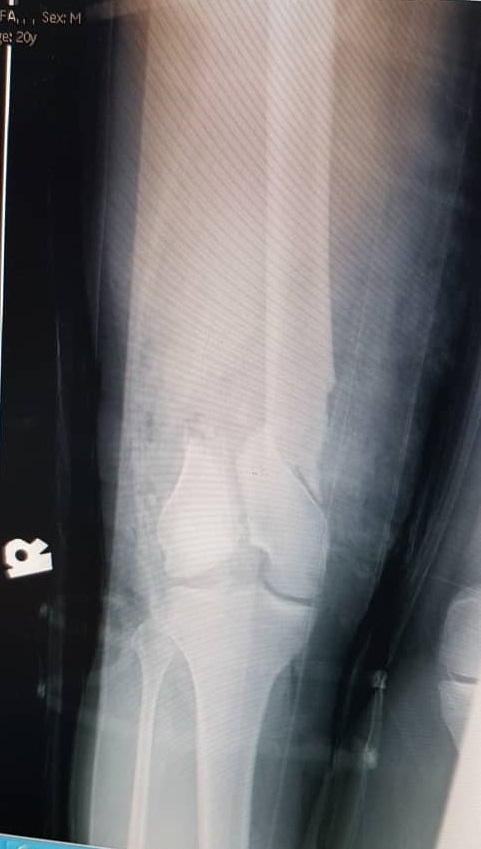

A 22-year-old man presented to our hospital in December 2020 following a motor vehicle accident. The patient had no significant medical, family, or allergy history. He worked in a metal factory and occasionally smoked. The sustained injuries included a closed fracture of the right neck of the femur, an open right supracondylar femur fracture (Gustilo 3C), and an open midshaft fracture of the right tibia (Gustilo 2) (Figures 1, 2, and 3).